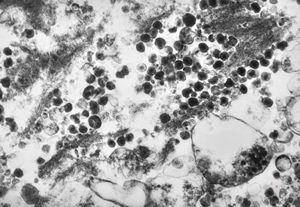

M,43y. | fungi in blood (Candida v.s.) - mycoseption